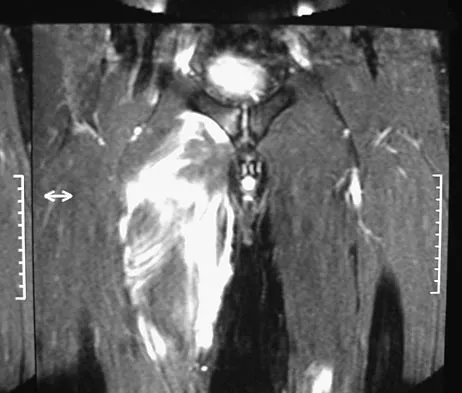

A 36-year-old professional baseball player reports the acute onset of severe right groin pain while attempting to avoid being hit by a baseball while at bat. Examination reveals tenderness, soft-tissue swelling, and ecchymosis in the right groin extending over the medial thigh. MRI scans are shown in Figures 8a and 8b. Management should consist of